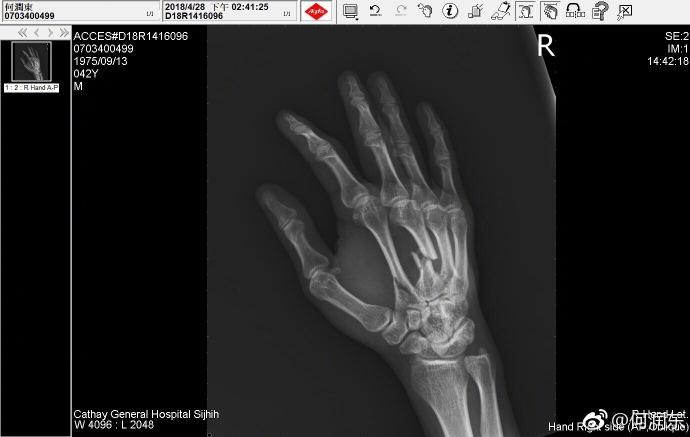

他受伤的伤情才不止这一点,另一张X光片明显看得出来有三根手指都做了固定处理。黑乎乎的阴影,看着也是让人毛骨悚然。

这般惨痛,没想到何润东心情似乎还是不错的,三根钢爪子已经有了,“当我能摆脱残障式健身的那一刻,我将升级为金刚狼。”